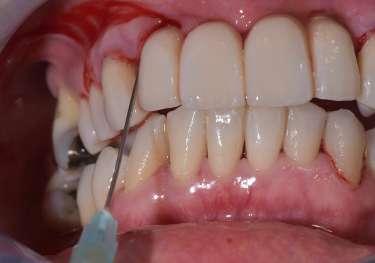

Trattamento di carie cervicale di elemento 1.5 con laser a Erbio

1 2

Paziente femmina, 38 anni che presenta carie cervicale dell’elemento 1.5. Gengivectomia con manipolo angolato, tip in zaffiro con diametro di 400 μm, lunghezza 12 mm, 2.4 W, 20 Hz, 120 mJ E per impulso, potenza di picco 750 W, densità di potenza media 659 W/cm2, densità di potenza di picco 205,860 W/cm2, energia totale 432 J, larghezza impulso 160 μs, distanza tip-tessuto 1 mm, 50% acqua, 50% aria, tempo totale di trafamento 180 sec. Impostazioni dello smalto: manipolo angolato, tip in zaffiro diametro 800 μm, lunghezza 12 mm, totale energia 810 J, ampiezza dell’impulso 160 μs, distanza tip-tessuto 1 mm, 100% acqua, 70% aria, tempo di trafamento totale 180 sec.

3 5 6

Impostazioni dentina e smear layer: tip in zaffiro con diametro 800 μm, lunghezza 12 mm, 3.3 W, 20 Hz, 165 mJ, potenza di picco 1031 W, densità di potenza media 360 W/cm2, densità di potenza di picco 112,346 W/cm2, energia totale 594 J, ampiezza dell’impulso 160 μs, distanza tip-tessuto 1 mm, 100% acqua (18 ml/min), 70% aria, tempo di trafamento totale 120 sec.

Fig. 1 – Cavità su 1.5 Fig. 2 – Particolare della cavità del dente 1.5 Fig. 3 – Preparazione Laser Er:YAG Pluser con lunghezza d’onda di 2940 nm di LAMBDA DoctorSmile, Italia. Fig. 4 – Particolare della cavità dopo gengivectomia Fig. 5 – Particolare della cavità completata dopo la preparazione della dentina Fig. 6 – Restauro finale in composito (Asteria Tokuyama, Japan)